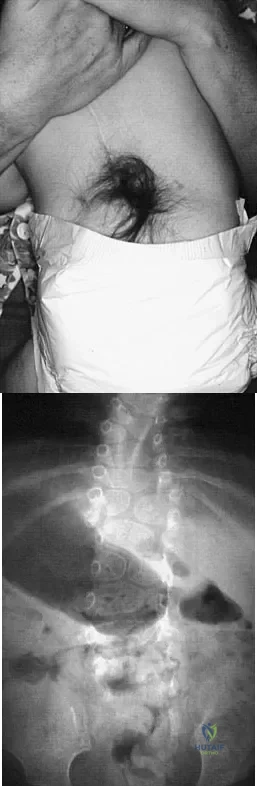

A 4-month-old infant is referred for evaluation of congenital scoliosis. The child has no congenital heart anomalies, and a renal ultrasound shows that he has one kidney. Examination reveals mild scoliosis and a large hairy patch on the child's back. Neurologic evaluation is normal for his age. A clinical photograph and radiograph are shown in Figures 19a and 19b. Initial management should consist of